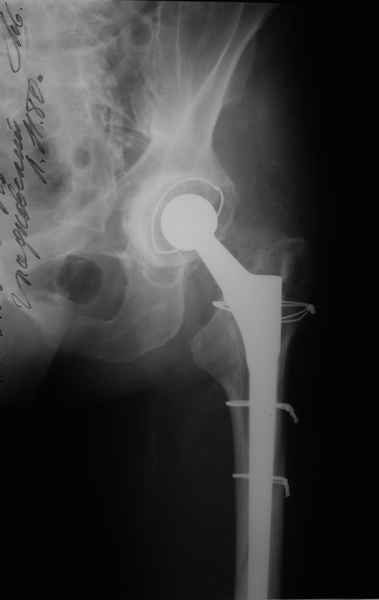

1.Остеосинтез на ножке. Мне кажется, что применительно к этому случаю малоперспективный вариант. Синтез хорош, когда можно его выполнить в малоинвазивном исполнении и достигнуть стабильности. Действительно, если ножка б/цементной фиксации после этого не будет иметь фиксации, то ревизия не будет иметь проблем. В представленном случае стабильность синтеза сомнительная, а проведение доп.иммобилизации приведет к контрактуре суставов.

2. Применение ножки дистальной фиксации, мы отдаем предпочтение ножке Вагнера с фиксацией проксимального отдела на ножке. Более травматичное вмешательство, но при стабильной фиксации ножки реабилитация идет в обычном режиме.

Хочется показать два подобных случая, П-ка З. 72 лет и п-т Г. 80 лет. Сразу принимаю замечание, что это были ножки цементной фиксации, просто под руками не было бесцементника.